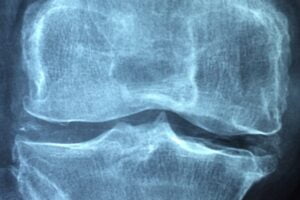

Síntomas de la Artralgia: Tratamiento y Formas de Controlarla. Foto por antoni-shkraba Pexels